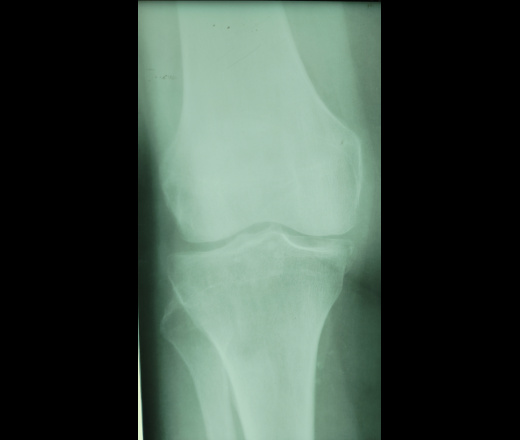

Здравствуйте! Женщина, 65. Из анамнеза - боль в коленях, больше слева. Смущает медиальный мыщелок большеберцовой кости. Как считаете, есть/был ди тут когда-то перелом? Очень странная форма.

Я за артроз и хондромные тела.

Я бы снял противоположный коленнный сустав, для сравнения. Какая-то нерезкость изображения? Надо разобраться в чем причина?